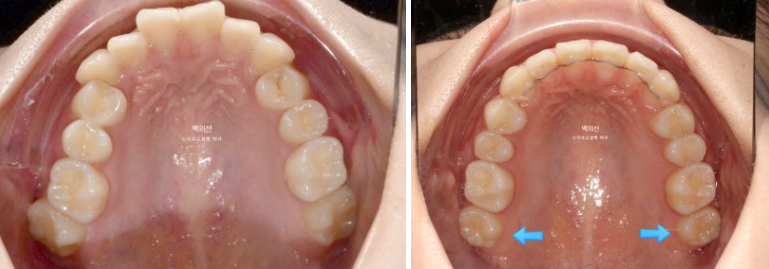

23.05

맨 뒤 큰어금니는 뒤로 나있습니다.

파란 화살표 위 마지막 큰어금니는 매복된 사랑니에 눌려 사랑니를 발치하지 않으면 바로세우기 힘든상황입니다.

그런데 씨티를 찍어보니 매복된 사랑니가 상악동과 닿아있어 발치가 쉽지 않은 상황입니다.

무리하게 발치를 시도했다가 상악동천공 등의 부작용이 생길 수 있습니다.

이런 경우 사랑니의 사이즈나 모양이 큰어금니와 비슷하면 맨뒤에 위치한 두번째 큰어금니를 빼고 그곳으로 사랑니 맹출을 유도하면 좋습니다.

파란화살표는 사랑니입니다.